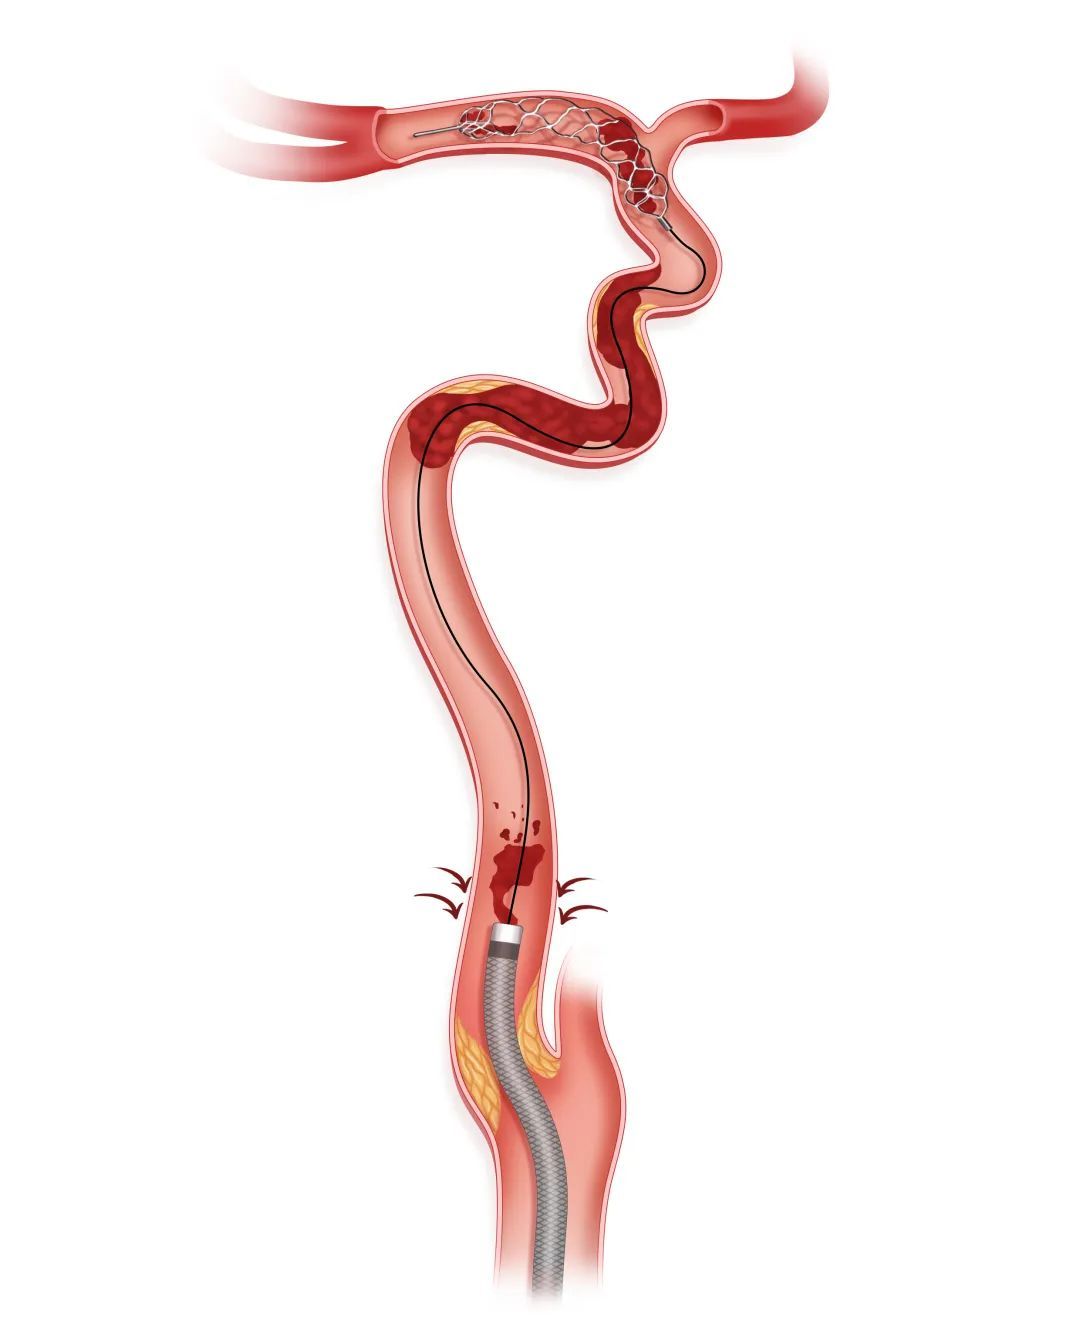

步骤二

造影初步鉴别病变性质

利用盲交换技术将微导管撤出体外,通过Tethys AS®血栓抽吸导管足量、足压力造影,初步鉴别闭塞段病变性质。